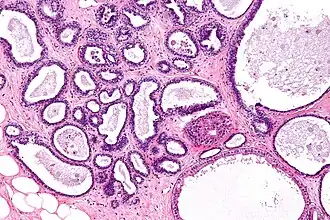

| Micrograph showing fibrocystic breast changes. H&E stain. | |